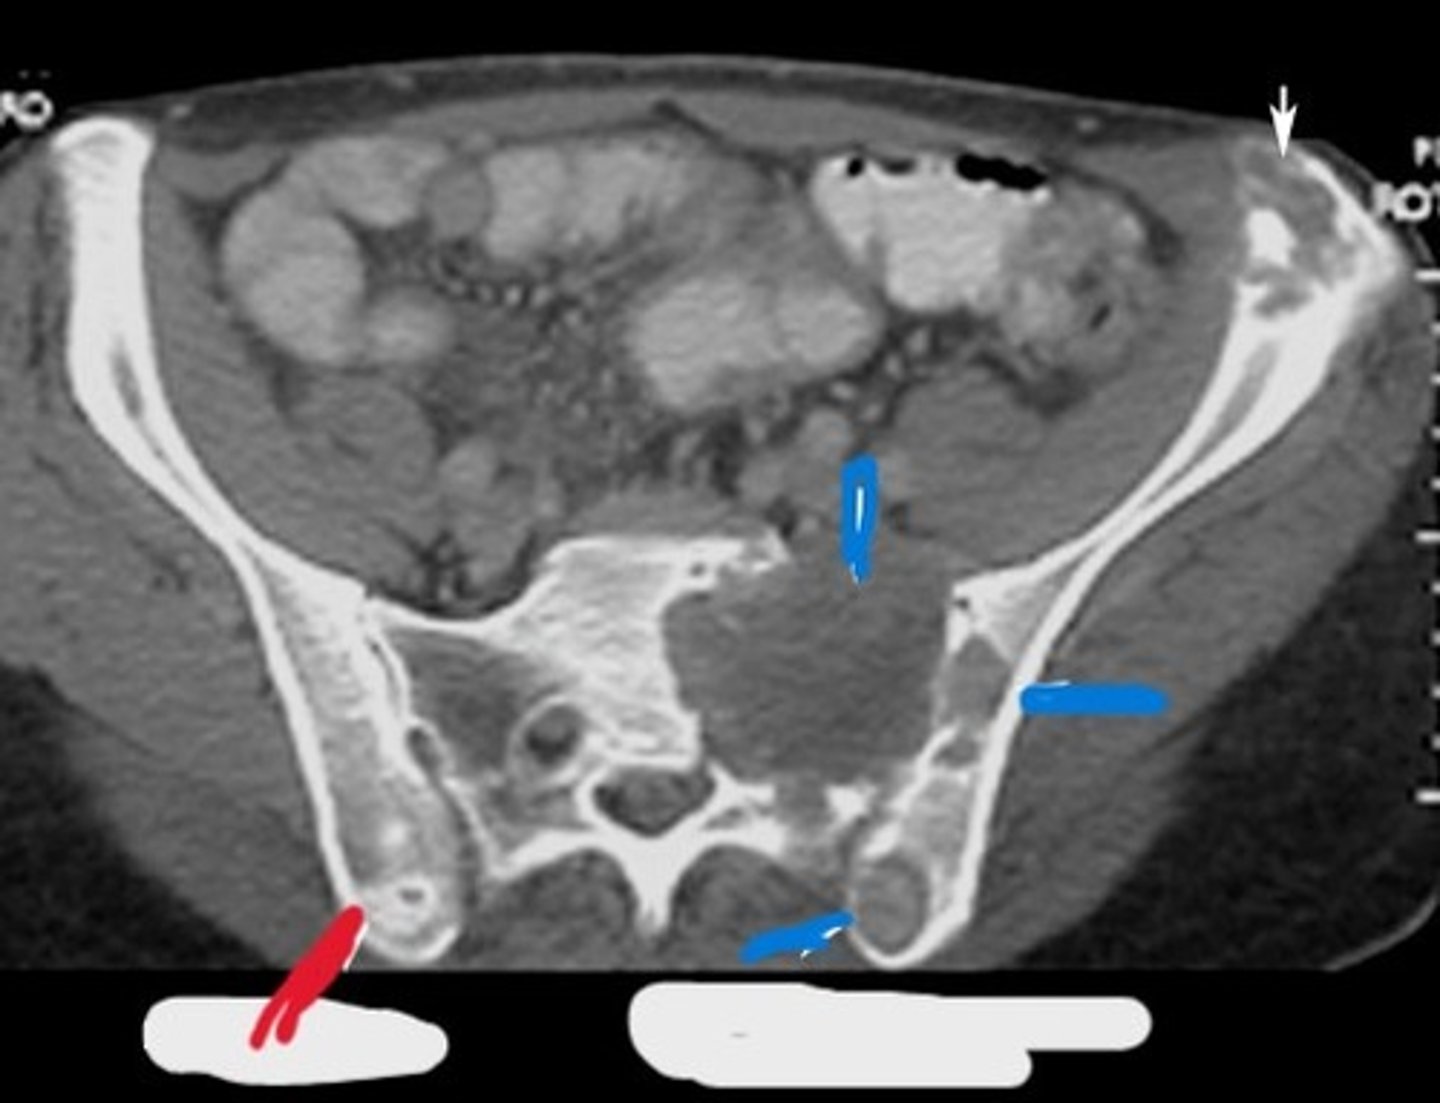

Red line- blastic lesion

Blue line- Lytic lesions

What type of pathology is the red line pointing to and what type of pathology is the blue line pointing to

Additive

What kind of pathology are blastic lesions

Destructive

What kind of pathology are lytic lesions

1) Left ilium

2) Left sacrum

Where is this pathology located (2)

Lytic (Destructive)

What type of pathology is this

1) Left pelvis

2) Left iliacus

3) Gluteus muscles

Where on the body is this pathology located (3)